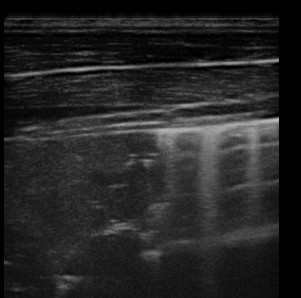

- Ultraschall: „Kometschweifartefakte“ als Hinweis auf Entzündungsprozesse